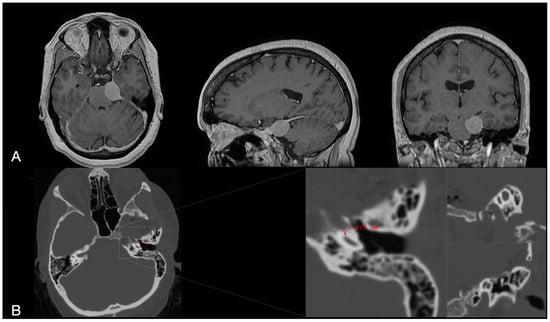

NIR Indocyanine–White Light Overlay Visualization for Neuro-Oto-Vascular Preservation During Anterior Transpetrosal Approaches: A Technical Note

Objectives: Anterior petrosectomy is a challenging neurosurgical procedure requiring precise identification and preservation of multiple critical structures. This technical note explores the feasibility of using real-time near-infrared indocyanine green (NIR-ICG) fluorescence with white light overlay to enhance visualization of the petrous internal carotid artery (ICA) during transpetrosal drilling. We aimed to assess its utility for planning and performing modified Dolenc–Kawase drilling. Methods: We integrated NIR-ICG and white light overlay using a robotic microscope with simultaneous visualization capabilities. This technique was applied to improve neurovascular preservation and skull base landmark identification. Intraoperative video frames and images were captured during an anterior transpetrosal approach for a petroclival meningioma, with technical details, surgical time, and feedback documented. Results: Real-time NIR-ICG with white light overlay successfully identified the posterior genu, horizontal petrosal segment, anterior genu, and superior petrosal sinus. It facilitated precise localization of cochlear landmarks, enabling tailored drilling of the Dolenc–Kawase rhomboid according to patient anatomy and accommodating potential anatomical variants. Conclusions: This approach could enhance intraoperative safety and improve exposure, possibly reducing neurovascular risks without extending operative time. It may serve as a valuable adjunct for complex skull base surgeries. Full article

Figure 1